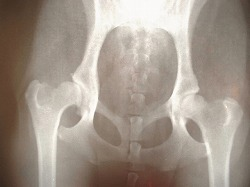

交通事故で脊髄損傷となった場合、脊椎の骨折を伴うことがあります。

脊髄は脊椎の中を通っていますので、骨折した骨片により脊髄を圧迫したり、時として脊椎を新たに損傷する危険性があります。

交通事故で脊椎が複雑骨折したり、脱臼で大きくずれていたり、骨粗しょう症などで骨がもろくなっている場合には、現状では脊髄損傷ではない部分まで脊髄損傷となったり、脊髄損傷の部分がさらに拡大する危険性があります。

それを防ぐ意味で、本人の骨盤から骨をとって脊椎に移植したり、金属のプレートを使ってボルトで固定するといった手術が行われます。